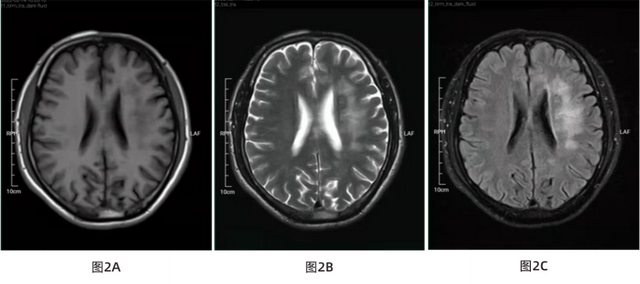

患者入院前2d无显着 诱因泛起左侧额颞部一连 性胀痛,呈阵发性,一连 10-20分钟不等,伴恶心吐逆 ,吐逆 为胃内容物。无肢体运动异常,无言语障碍,行头颅CT检查示左额叶异常信号。头颅MRI+增强示左侧额顶部颅骨皮下软组织变薄(图1),左侧侧脑室旁、额顶叶皮质下可见片状异常信号,增强扫描未见异常强化(图2)。既往患者于20岁时首次发现左侧额面部点片样瘢痕皮损,逐渐希望 扩大,未诊断。

入院体检:患者左侧头皮、额面部刀疤样皮损伴局部脱发,照片经本人知情赞成 后刊出(图3)。

图1 A T1WI矢状位前额局部头皮脂肪层变薄、消逝 (如图红色箭头所示);图1B T1WI冠状位左前额局部头皮脂肪层变薄、消逝 (如图红色箭头所示);图1C T2WI轴位左前额局部头皮脂肪层变薄、消逝 (如图红色箭头所示)

图2 A T1WI轴位左额顶叶皮层下白质低信号;图2B T2WI轴位左额顶叶皮层下白质高信号;图2C T2WI压水相左额顶叶皮层下白质高信号;图2D DWI左额顶叶皮层下白质稍高信号;图2E ADC相左额顶叶皮层下白质稍高信号;图2F T1WI增强无强化